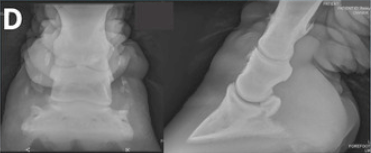

RX Images

In the 2013 Verena K. Affolter (U.C.Davis) study into CPL in Draft Horses there is a brief list of other potential diagnostics including lymphoscintigraphy and lymphangiogram. These procedures are expensive, invasive and unnecessary. Radiographs will show the extent of the folds but again are a surplus cost and show nothing that we can’t already see and feel, with regards to the CPL.

Hooves can be affected too. Coronary band dystrophy could present with hyperkeratosis and hypertrophis. Some CPL horses have poor hoof quality and some may develop laminitis. Persistent, treatment-resistant thrush and abscesses are common.